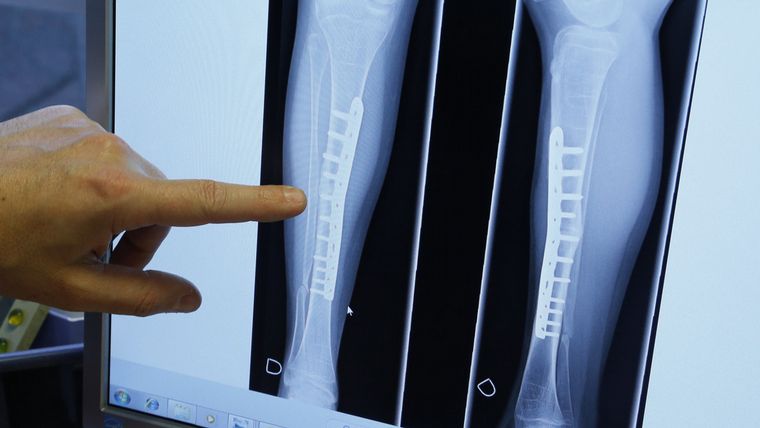

Un estudio publicado en la revista BMC Medicine concluyó que "las personas que no comen carne, especialmente las veganas, tienen un mayor riesgo de fracturas totales o en algunas áreas específicas, en particular la cadera".

El trabajo, realizado por un equipo de investigadores de las universidades británicas de Oxford y Bristol, detalla que, quienes no consumen productos de origen animal presentan un 43% más de posibilidades de fracturas, con un riesgo específico más elevado en las caderas, las piernas y las vértebras.

Durante la media de 18 años que se prolongó el seguimiento a cada uno de ellos, se registraron 3.941 fracturas en total, incluidas 566 en brazos, 889 en muñecas, 945 en caderas, 366 en piernas, 520 en tobillos y 467 en clavícula, costillas o vértebras.